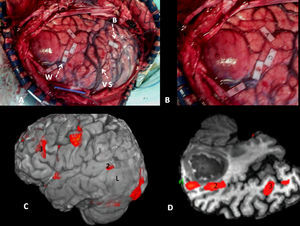

In the case of subcortical “functional” fasciculi, there was 100% concordance. The correlated bundles were (Table 3) (Fig. 2):

Arcuate fasciculus: medial part of the superior longitudinal fasciculus, connecting the frontal lateral and parietotemporal.

Frontoparietal fasciculus or bundle: lateral part of the superior longitudinal fasciculus, connecting Broca's area with the lower parietal lobe.

Lower frontooccipital fasciculus: it connects medial occipito-temporoparietal and prefrontal areas. In its anterior third it is located cranially to the ceiling of the temporal horn and the optic radiations. In its posterior temporooccipital segment it is lateral in relation to the ventricular occipital horn, becoming part of the sagittal stratum. It ends in the medial temporoccipital cortex.

Lower longitudinal fasciculus: in its left temporooccipital tract it is involved in identifying the form of objects or “visual object-form area”.

Subcallous fasciculus: it surrounds the ventricular frontal horn and connects the supplementary motor area with the cingulum and the caudate nucleus.

Another bundle identified was the uncinate fasciculus (Fig. 2) which connects the anterior frontotemporal cortex, which apparently is not involved in language. It serves as point of reference in locating the lower frontooccipital fasciculus and it is the point of departure for Meyer's ansa and the optic radiations (Fig. 3) (posterior temporooccipital tract forming part of the sagittal stratum, it lies laterally to the occipital horn, with a medial curvature toward the calcarine fissure).

Cortical correlation between functional MR and the surgical electrical mapping in the same patient from Fig. 4. (A) Intraoperative mapping. Patient in right lateral recumbent position. 4: Motor facial cortex; 3: Premotor cortex; 5, 6: Broca's area; 8: Frontal eye field. Correlation with functional MR (B, C and D): activation areas coincidental with cortical mapping. *Supplementary motor area. A: anterior; P: posterior.

Subcortical correlation between diffusion tensor image (DTI) and the surgical electrical mapping in the same patient from Figs. 4 and 5. (A) Intraoperative subcortical mapping. Patient in right lateral recumbent position. 41: Lower frontooccipital fasciculus (LFOF). (B) Cortical correlation with functional MR: 3: premotor cortex; 5: Broca's area; 8: frontal eye field. 3D-DTI sagittal reconstructions of LFOF. (C and D) The posterior margin of the LFOF (41) (arrow) limits posterior resection of tumor.